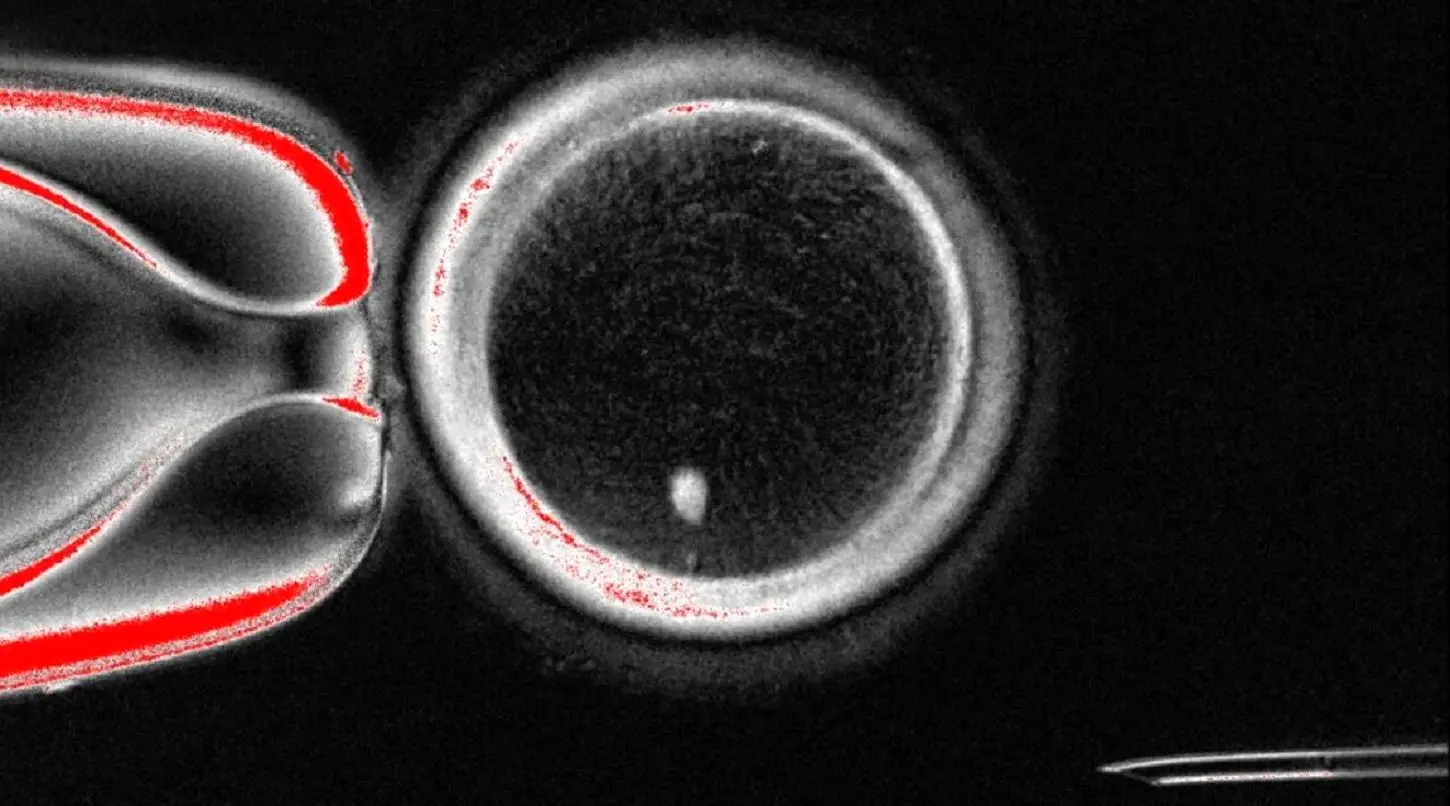

نشریه اکونومیست به‌تازگی از پژوهشی تازه نوشته که می‌تواند مشکل نبود تخمک در زنان را حل کند. دانشمندان می‌توانند برای نخستین بار، تخمک‌های بارور انسانی را از سلول‌های پوستی تولید کنند.

پژوهشی که در دانشگاه اورگان در حال بررسی است، از روشی به اسم انتقال هسته سلول سوماتیک (SCNT) بهره گرفته؛ همان روشی که برای شبیه‌سازی گوسفند معروف به اسم «دالی» به کار رفته بود. این روش از این قرار است:

• ابتدا هسته تخمک‌های اهدایی خارج می‌شوند.

• سپس هسته سلول‌های پوستی داوطلبان در این تخمک‌ها جای‌گذاری می‌شوند.

این بار، هدف تولید جنین نبوده بلکه صرفا به دنبال تولید تخمکی قابل باروری بوده‌اند.

در این روش، سلول پوستی، 46 کروموزوم را وارد تخمک می‌کند و فضا برای اسپرم باقی نمی‌ماند. راه‌کار دانشمندان استفاده از روشی ابتکاری به اسم «میتومئوز» است. یعنی:

• هسته سلول درست قبل از دو برابر شدن کروموزوم‌ها وارد تخمک می‌شود.

• سپس تقسیم سلولی به صورت زودهنگام القا می‌شود تا تعداد کروموزوم‌ها به 23 مورد کاهش یابد.

نتیجه اینکه از میان 82 تخمک تولیدشده، پنج مورد توانستند به مرحله‌ای از رشد جنین برسند و این انقلابی بزرگ در علم باروری به شمار می‌آید.